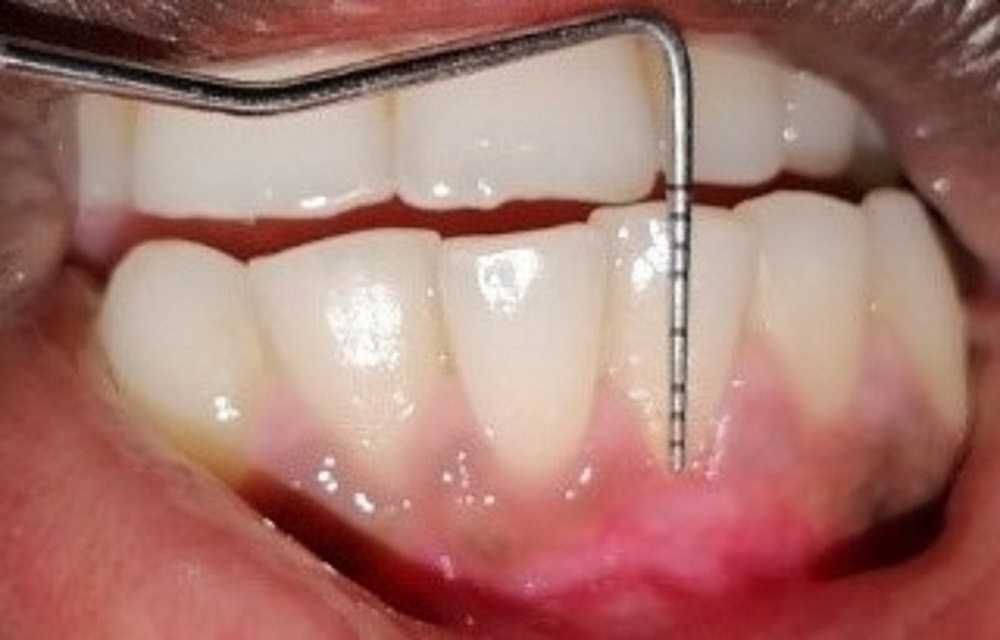

Patients with Miller’s class I and II recession defects on the anterior teeth, with the probing depth (PD) >3 mm, the clinical attachment loss (CAL) >5 mm and the keratinized tissue width (KTW) >2 mm, were included in the study. Pregnant and lactating women, smokers, systemically compromised patients, subjects who had undergone the periodontal therapy in the last 6 months, and those who were on antibiotics 3 months prior to commencing the study (confirmed while recording the case history) were excluded from the study.

The recession depth, GT, PD, CAL, and KTW were assessed using a Williams probe at baseline (D0), and 3 months (D3) and 6 months (D6) post-surgery, whereas PRC was assessed at 3 months (D3) and 6 months (D6) post-surgery. The VAS score and WHI were estimated 1 week after surgery.

Group A comprised 12 patients who underwent surgery to treat their denuded roots by CAF and PRF application (Figure 2).

The mean RD at D0, D3 and D6 was 2.54 mm, 1.96 mm and 1.70 mm, respectively. It was observed that the RD values decreased significantly at D6 as compared to D0 (p < 0.001). The mean CAL at D0, D3 and D6 was 4.19 mm, 3.49 mm and 3.19 mm, respectively, and the values also decreased significantly between D0 and D6 (p < 0.001). The mean GT at D0, D3 and D6 was 1.43 mm, 1.53 mm and 1.57 mm, respectively, and the GT values increased significantly from D0 to D3 and from D3 to D6 (p < 0.05). The mean KTW at D0, D3 and D6 was 1.97 mm, 2.65 mm and 2.93 mm, respectively. There was a significant increase in the KTW values from D0 to D6 (p < 0.05). The mean PD at D0, D3 and D6 was 1.65 mm, 1.43 mm and 1.47 mm, respectively. There was no significant change from D0 to D6 for the PD values (p = 0.127). The mean PRC at D3 and D6 was 22.63% and 34.00%, respectively. There was no significant change in the PRC values between D3 and D6 (p = 0.131). Therefore, there was improvement at different time points for the parameters RD, GT, CAL, and KTW, but the PD and PRC values did not improve (Table 1).